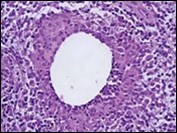

Figure 2.Granulomatous mastitis with articulated epitheloid cell granuloma, lymphocytic, plasma cell and neutrophilic infiltration10.

Granulomatous mastitis with articulated epitheloid cell granuloma, lymphocytic, plasma cell and                   neutrophilic infiltration10.

Core needle biopsy of idiopathic granulomatous mastitis enunciates multiple aggregates of non- caseating epitheloid cell granulomas within and encompassing breast lobules, constituted of epitheloid histiocytes, lymphocytes, neutrophils and multinucleated giant cells. Granulomatous inflammation is predominantly lobulo-centric. The inflammation is preponderantly composed of lymphocytes, plasma cells, epitheloid histiocytes, multinucleated giant cells and neutrophils. Neutrophils can configure micro-abscesses and encompass vacant micro-cystic cavities, morphological features which are in common with cystic neutrophilic granulomatous mastitis. Non specific lobulitis along with a lymphoid and plasma cell infiltrate accompanies the granulomatous inflammation. Necrosis is usually absent. Neutrophilic micro-abscesses can be accompanied by fistula formation 4, 5.

Multinucleated giant cells are detected in an estimated three fourths (78.5%) instances. Plasma cells are discernible in around half (53.9%) of the subjects and usually appear at the margins of cystic vacuoles with centric accumulation of neutrophils within the granulomas.